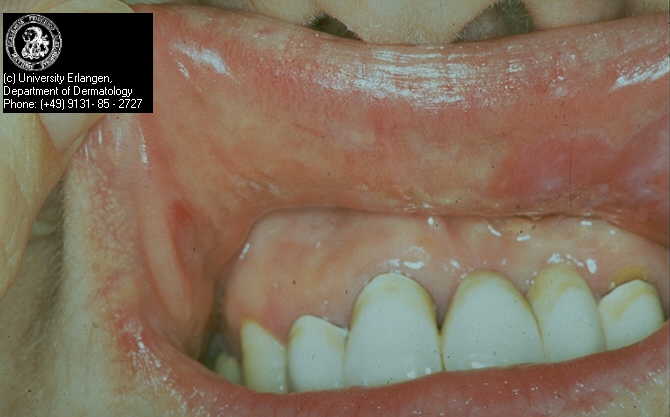

Manige Fartasch, M.D.